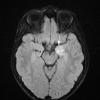

NEOPLASMS (NEURONAL)

Multinodular Vacuolating Neuronal Tumor (3)